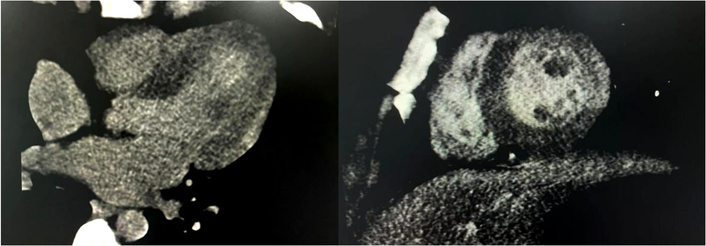

Full blood count: WBC 11.65 × 109/L, neutrophil count 8.19 × 109/L, NT-proBNP 397.1 pg/mL, cTnI 8.08 ng/mL, Myo 25.4 ng/mL, CK-MB 90.6 ng/mL, CRP 60.3 mg/L. ECG demonstrated ST-segment depression. A transthoracic echocardiogram performed 1 day after admission showed no focal wall motion abnormalities and a normal ejection fraction of 60%. CT coronary angiography performed on the same day showed normal coronary anatomy with no CAD, no wall motion abnormalities. Three-minute early delayed enhancement CT imaging demonstrated a focus of enhancement in the subcardia and predominantly involving the lateral wall of the left ventricle (Figure 2). A subsequent cardiac MRI performed 7 days later showed delayed myocardial enhancement seen on the CTA. After resolution of his symptoms and normalization of his cardiac enzymes and function, the patient was discharged home on day 7 with the presumptive diagnosis of viral myopericarditis.

Three-minute early delayed enhancement CT imaging demonstrated a focus of enhancement in the subcardia and predominantly involving the lateral wall of the left ventricle.